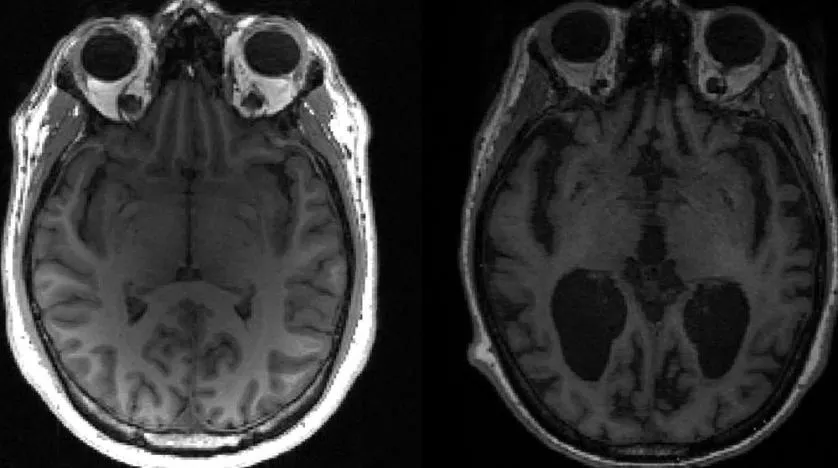

This undated image courtesy of, Dr. Timothy Rittman, University of Cambridge, shows an MRI image of a healthy brain (L) and an Alzheimer's brain (R) with large black gaps where brain has shrunk. (AFP)

In Alzheimer's disease, two key proteins, tau and amyloid beta, build up into tangles and plaques, known together as aggregates, which cause brain cells to die and lead to brain shrinkage.